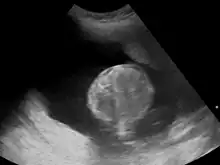

Polyhydramnios is a medical condition describing an excess of amniotic fluid in the amniotic sac. It is seen in about 1% of pregnancies.[1][2][3] It is typically diagnosed when the amniotic fluid index (AFI) is greater than 24 cm.[4][5] There are two clinical varieties of polyhydramnios: chronic polyhydramnios where excess amniotic fluid accumulates gradually, and acute polyhydramnios where excess amniotic fluid collects rapidly.

During the pregnancy, certain clinical signs may suggest polyhydramnios. In the mother, the physician may observe increased abdominal size out of proportion for her weight gain and gestation age, uterine size that outpaces gestational age, shiny skin with stria (seen mostly in severe polyhydramnios), dyspnea, and chest heaviness. When examining the fetus, faint fetal heart sounds are also an important clinical sign of this condition.